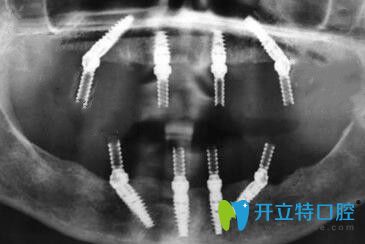

從面診到拍CT片、身體的多種常規(guī)檢查等,一樣不漏;統(tǒng)統(tǒng)做完后才制定修復(fù)方案。方醫(yī)生說從各種檢查情況來看,我比較適合做全口ALL-ON-4種植牙,這樣不僅省錢,手術(shù)速度快、創(chuàng)傷也很小。

還沒等方醫(yī)生制定完種植方案,我都著急要做種植牙(想盡快長(zhǎng)出“新牙”);手術(shù)中醫(yī)生的操作手法很輕也很熟練,所以整個(gè)種植過程中沒有感覺到明顯的疼痛~~~

種植牙術(shù)后先戴的是臨時(shí)牙冠,但是不耽誤正常吃飯,只是比較硬的東西暫時(shí)不能啃~~~下面是2周后戴全瓷牙冠的照片▼,整個(gè)人看上去是不是年輕了很多呢!